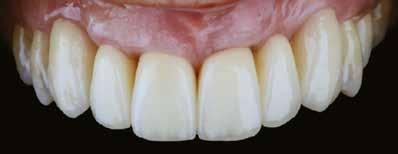

10. a ábra: Végleges lítium-diszilikát koronák. – 10. b ábra: Végleges monolitikus cirkónium-dioxid korona. – 11. a–b ábrák: Klinikai megjelenés tizenkét hónap elteltével. 12. a–b ábrák: Tizenkét hónapos kontrollröntgen-felvételek.